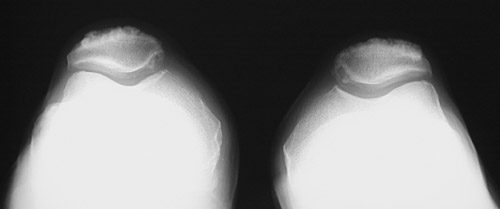

![]() | This series of knee radiographs reveals extensive chondrocalcinosis involving the menisci and articular cartilage. Note particularly the chondrocalcinosis of the meniscus above. Chondrocalcinosis is a condition related most to aging with calcium pyrophosphate dihydrate (CPPD) crystal deposition. The relationship to osteoarthritis is not clear, but CPPD disease can contribute to osteoarthritic changes, which are also present in these radiographic views. In the case shown here, bone density is not decreased. |